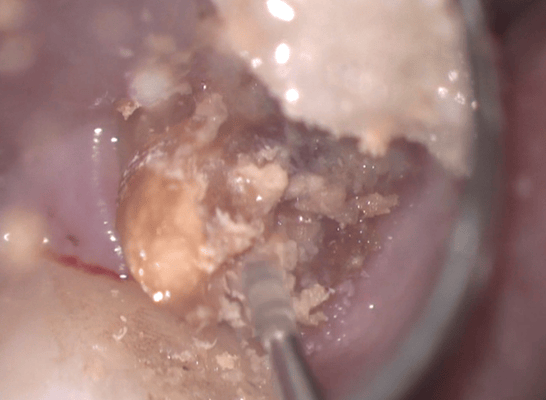

他院では抜歯と診断された歯ですが、それも間違えではありません。しかし、歯肉圧排をしたりすれば、保存できる可能性があることも多くあります。最初の状態ではラバーダム施すことが困難です。虫歯を除去中に歯髄の一部が露出しましたが、隔壁を作製し、防湿ができる環境を作って、歯髄を除去せずに保存できました。

クラウンを外すと、歯肉縁下までの大きな虫歯が確認できます。ラバーダムができないので、簡易防湿を行い、歯肉溝からの浸出液の侵入を防ぎます。隣の歯の間にまたがる虫歯ですが、丁寧に軟化象牙質を除去します。歯髄の露出はありましたが、特殊なセメントで緊密にシール(絆創膏みたいなもの)します。歯髄を除去せずにすみました。